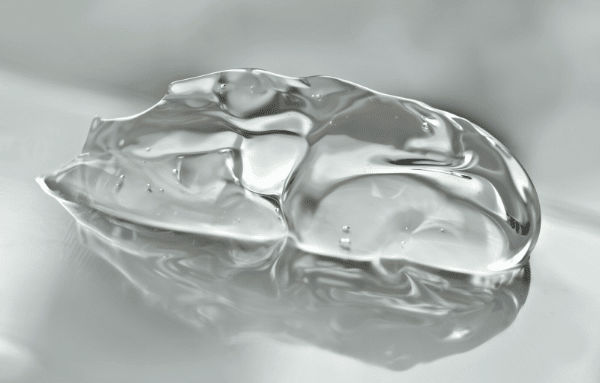

Au centre de l’œil, un gel transparent, le vitré, occupe près de 80 % du volume de l’organe. Ce gel, attaché à la rétine par des fibres microscopiques, assure la cohésion interne de l’œil. Un décollement postérieur du vitré, souvent abrégé en DVP, se définit par la séparation du vitré de la rétine, modifiant l’équilibre fragile de la structure oculaire.

Le vitré, à première vue anodin, est en réalité une matrice complexe : 99 % d’eau, 1 % d’acide hyaluronique et de collagène insoluble. S’y ajoutent glycoprotéines, protéines solubles et une population cellulaire nommée hyalocytes. Ce fragile équilibre assure au vitré sa transparence et sa consistance si particulière.

Avec l’âge, un changement s’opère : le vitré devient moins homogène, moins solide, et tend à se liquéfier. Cette transformation, connue sous le nom de liquéfaction vitréenne, rétrécit le gel et le détache progressivement de la rétine. Lorsque les fibres qui relient le vitré à la rétine cèdent, le vitré finit par se séparer totalement, déclenchant le fameux DVP.

Le processus de synérèse du vitré : effondrement et évolution

Chez les plus jeunes, le vitré reste dense et homogène, avec un centre lisse et une périphérie plus compacte (le cortex). Avec le temps, la liquéfaction s’installe, des cavités de liquide (lacunes) se forment, d’abord au centre puis ailleurs dans la matrice du gel. Ces zones liquides, entourées de condensations fibrillaires, fusionnent progressivement. Les réseaux de collagène et d’acide hyaluronique se dégradent, créant une grande cavité centrale. Cette instabilité mécanique fragilise la connexion du vitré à la rétine, particulièrement près du nerf optique, et aboutit à un DVP qui s’étend ensuite vers la périphérie.